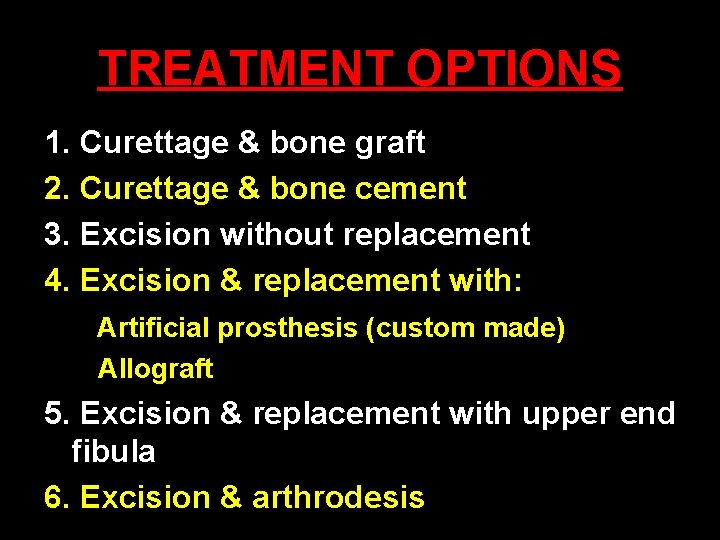

TREATMENT OPTIONS 1. Curettage & bone graft 2. Curettage & bone cement 3. Excision without replacement 4. Excision & replacement with: Artificial prosthesis (custom made) Allograft 5. Excision & replacement with upper end fibula 6. Excision & arthrodesis